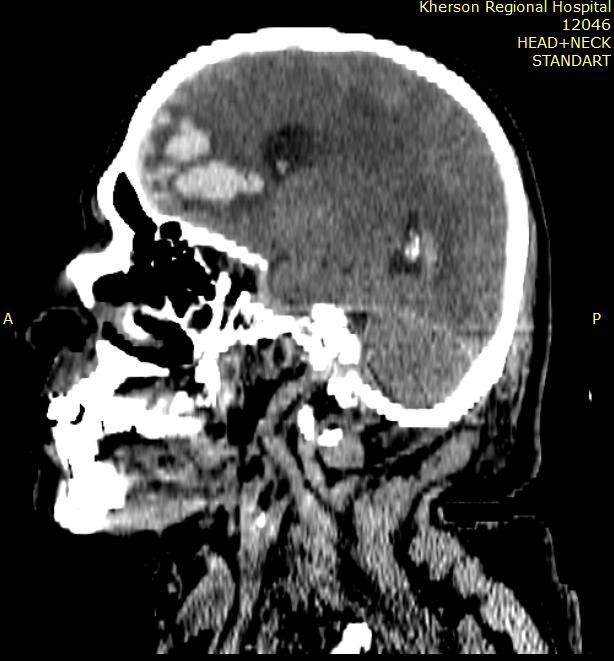

ДАП зумовлений дифузно розширеними по мозковим структурам розривами аксонів та дрібновогнищевими крововиливами.

Зазвичай пошкоджується:

- стовбур мозку,

- мозолисте тіло,

- біла речовина півкуль

- та перивентрикулярні ділянки.